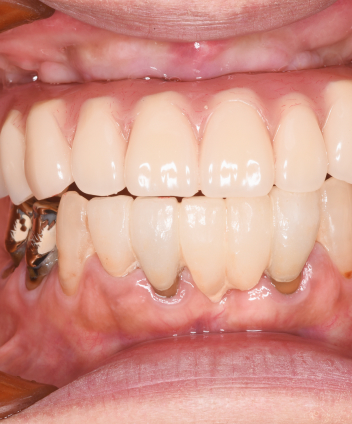

Treatment Case

Treatment

Case